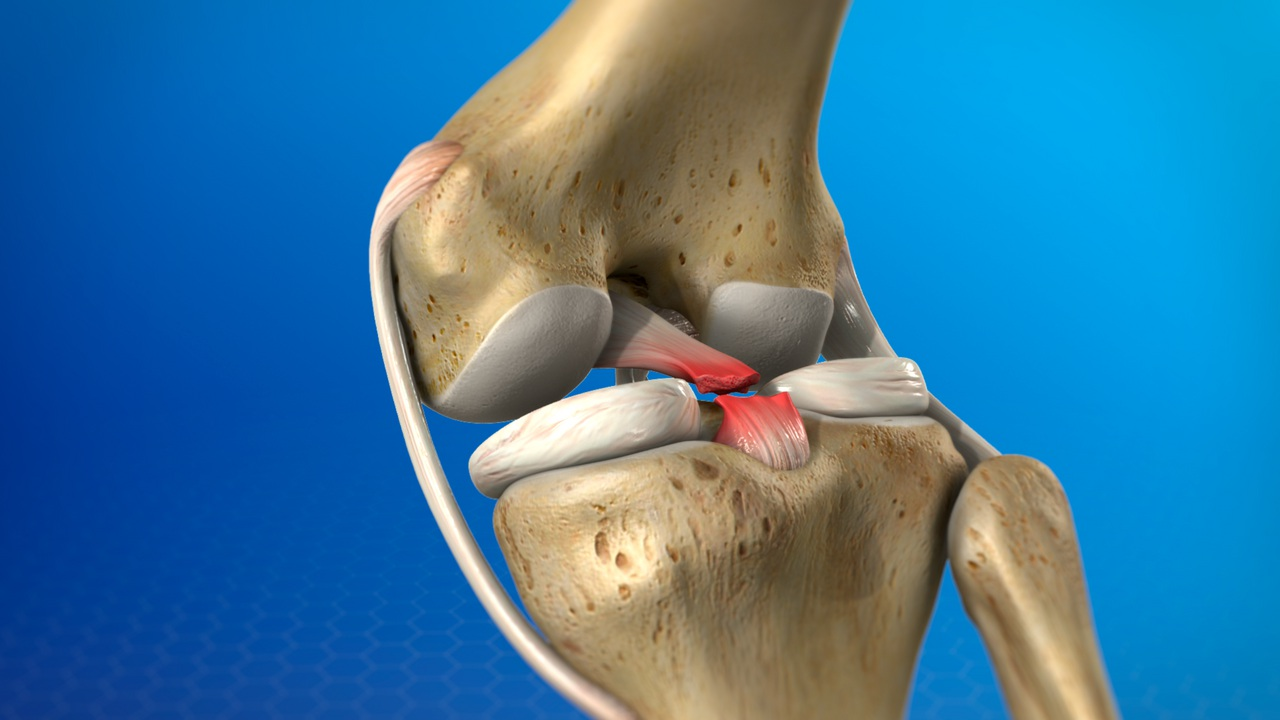

What Is a PCL Injury?

The posterior cruciate ligament (PCL) is one of the main stabilizing ligaments of the knee. It connects the thigh bone (femur) to the shin bone (tibia) and prevents the tibia from moving backward relative to the femur.

A PCL injury occurs when this ligament is overstretched or torn, leading to posterior instability of the knee.